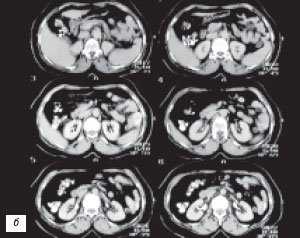

(Слева) УЗИ, продольная плоскость сканирования: гипоэхогенное «объемное образование» в центре, которое выступает в почечную лоханку.

(Справа) КТ с контрастированием, аксиальная проекция: у этого же пациента установлено, что «объемное образование» — это нормальное корковое вещество почки, которое инвагинирует в почечную лоханку между чашечками верхнего полюса и меж полюсной областью почки. Обратите внимание на нормальный внешний контур почки. Бертиниевы колонны чаще всего выявляют с одной стороны и слева, как в данном случае: в 18% случаев они могут быть двусторонними.